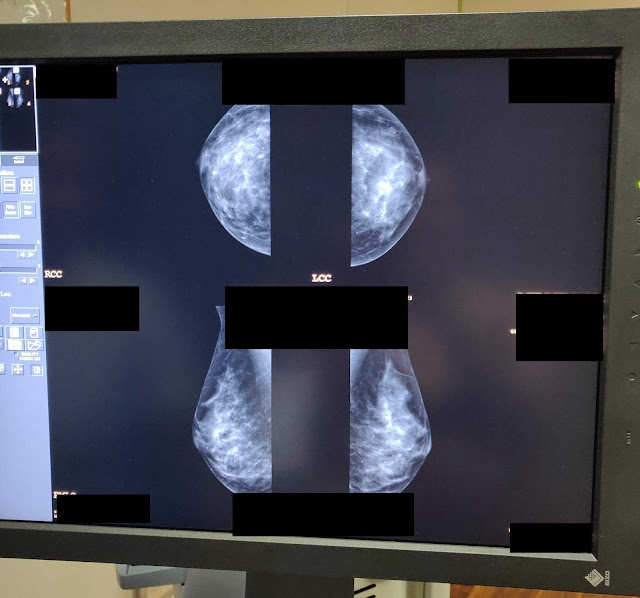

![]() |

| The only picture of my boobs on the internet to date. |

My mom told me that she has dense breast tissue and needs to have an ultrasound after her mamogram as part of her annual appointment. I was worried this would be the case for me but the nurse who performed my mamogram didn’t think this would be the case based on my images. My friend who’s mom had breast cancer informed me that in the US, patients are often called back for another mamogram after their initial one as there is no baseline to compare the x-ray to. I haven’t heard of this happening in the UK though.